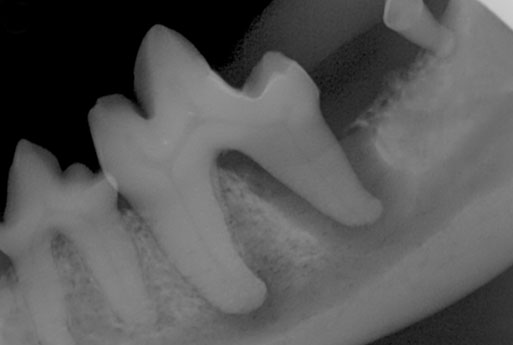

Dental x-rays are a 2-D projection of the bony structures that comprise the tooth and the bone supporting the roots. They give an overview of a region in the mouth, allowing for the evaluation of several structures at once. Taking x-rays during a procedure is an effective way to evaluate the progress of surgery. Additionally, we take postoperative x-rays each time we extract a tooth to document that region without the tooth present and to ensure no roots have been left behind. State-of-the-Art Dental Imaging See Beneath The Surface Imaging is a significant part of accurately diagnosing and treating your pet’s dental disease. The standard of veterinary dental care is to use full-mouth dental x-rays to evaluate the portions of the tooth below the gumline. More and more veterinary dental specialists are using Cone Beam Computed Tomography as a more thorough and comprehensive diagnostic tool. We are among the specialists who use this technology. Dental X-Rays

Cone Beam CT is a 3-D imaging tool that allows us to evaluate not only the teeth and supporting bones, but the entire skull (nose, upper and lower jaws, and jaw joints), including the soft tissues (lymph nodes, tongue, eyes, and ears). This enhanced comprehensive understanding gives us the ability to quickly and accurately diagnose and treat your pet. Using Cone Beam CT technology has allowed us to reduce the amount of time needed for imaging under anesthesia, as well as minimizing radiation exposure. It is a much more sensitive tool, enabling us to catch problems earlier and triangulate their exact location. Cone Beam Computed Tomography